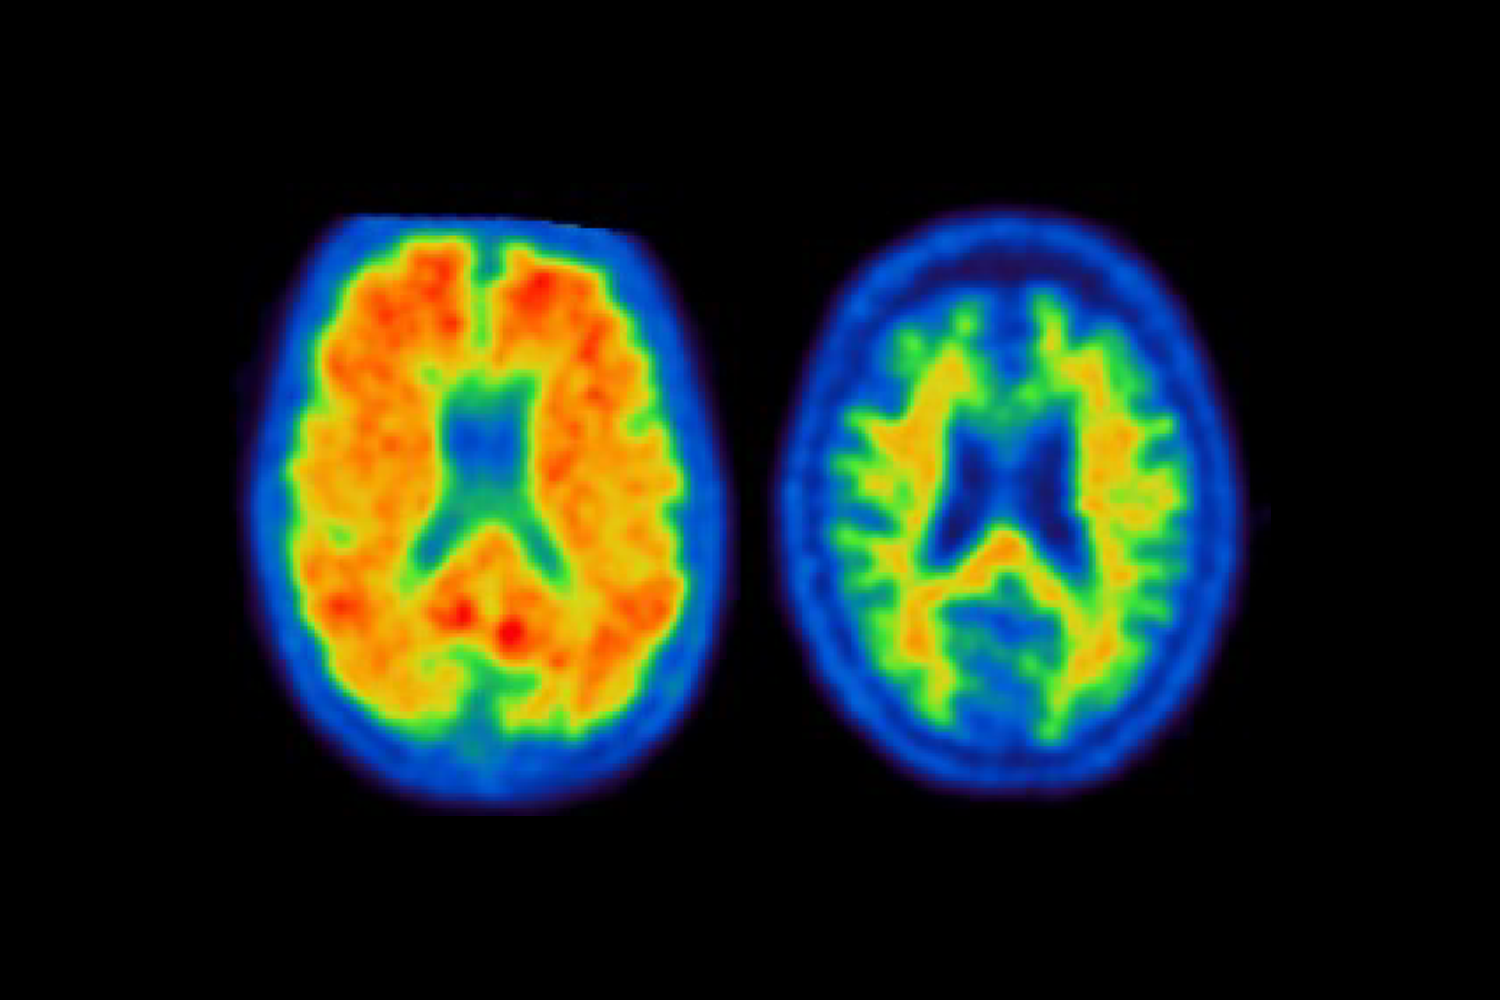

Novel strategy for biomarker-based amyloid diagnostics in clinical settings

A new collaborative study coordinated by LMU/SyNergy investigators and the University of Vienna proposes a novel clinical workflow for the reliable biomarker-based identification of amyloid pathology in memory clinic patients, in preparation of disease-modifying treatments against Alzheimer’s disease